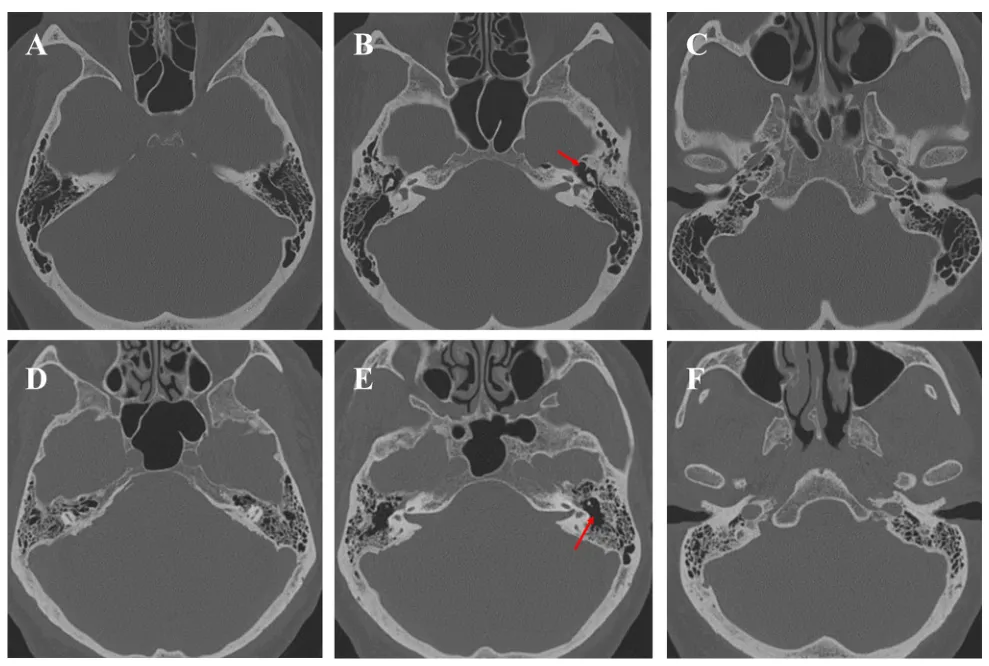

岩骨气化程度的高低,加上乙状窦、颈静脉球、半规管和面神经周围骨质厚度的差异,直接决定了外科医生在该环节的操作信心与推进速度。当乳突气化充分时,区分松质骨与皮质骨相对容易;而在气化不良的情况下,神经导航系统成为保护半规管、耳蜗和面神经的关键辅助工具。此外,无论岩骨气化程度如何,鼓窦入口作为一个恒定存在的解剖标志,都必须在启动磨骨前通过CT扫描加以确认。

图3. 岩骨气化程度。轴位CT扫描显示两个病例,分别为高度气化(A–C)和低度气化(D–F)的岩骨。在所有病例中,鼓窦入口的存在都是一个恒定结构(红色箭头)。

颈静脉球的意外损伤是乳突切除术中最具灾难性的并发症之一。高位颈静脉球有时距离后半规管和内听道极近,一旦误伤后果不堪设想。因此在开始乳突切除前,务必通过冠状位MRI和CT扫描明确颈静脉球的高度状态——这不仅让术者对高风险区域保持警觉,更重要的是提示迷路下通道空间受限,此时经岩后入路可能并非最优选项。